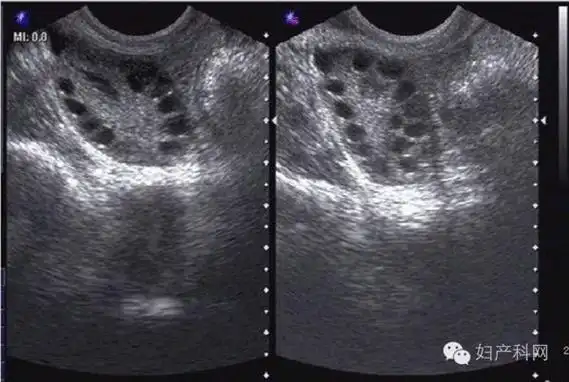

多囊卵巢是b超检查发现卵巢呈多囊样改变:一侧或双侧卵巢直径2-9mm的

3,多囊卵巢,单侧或双侧有大于或等于12个小卵泡.